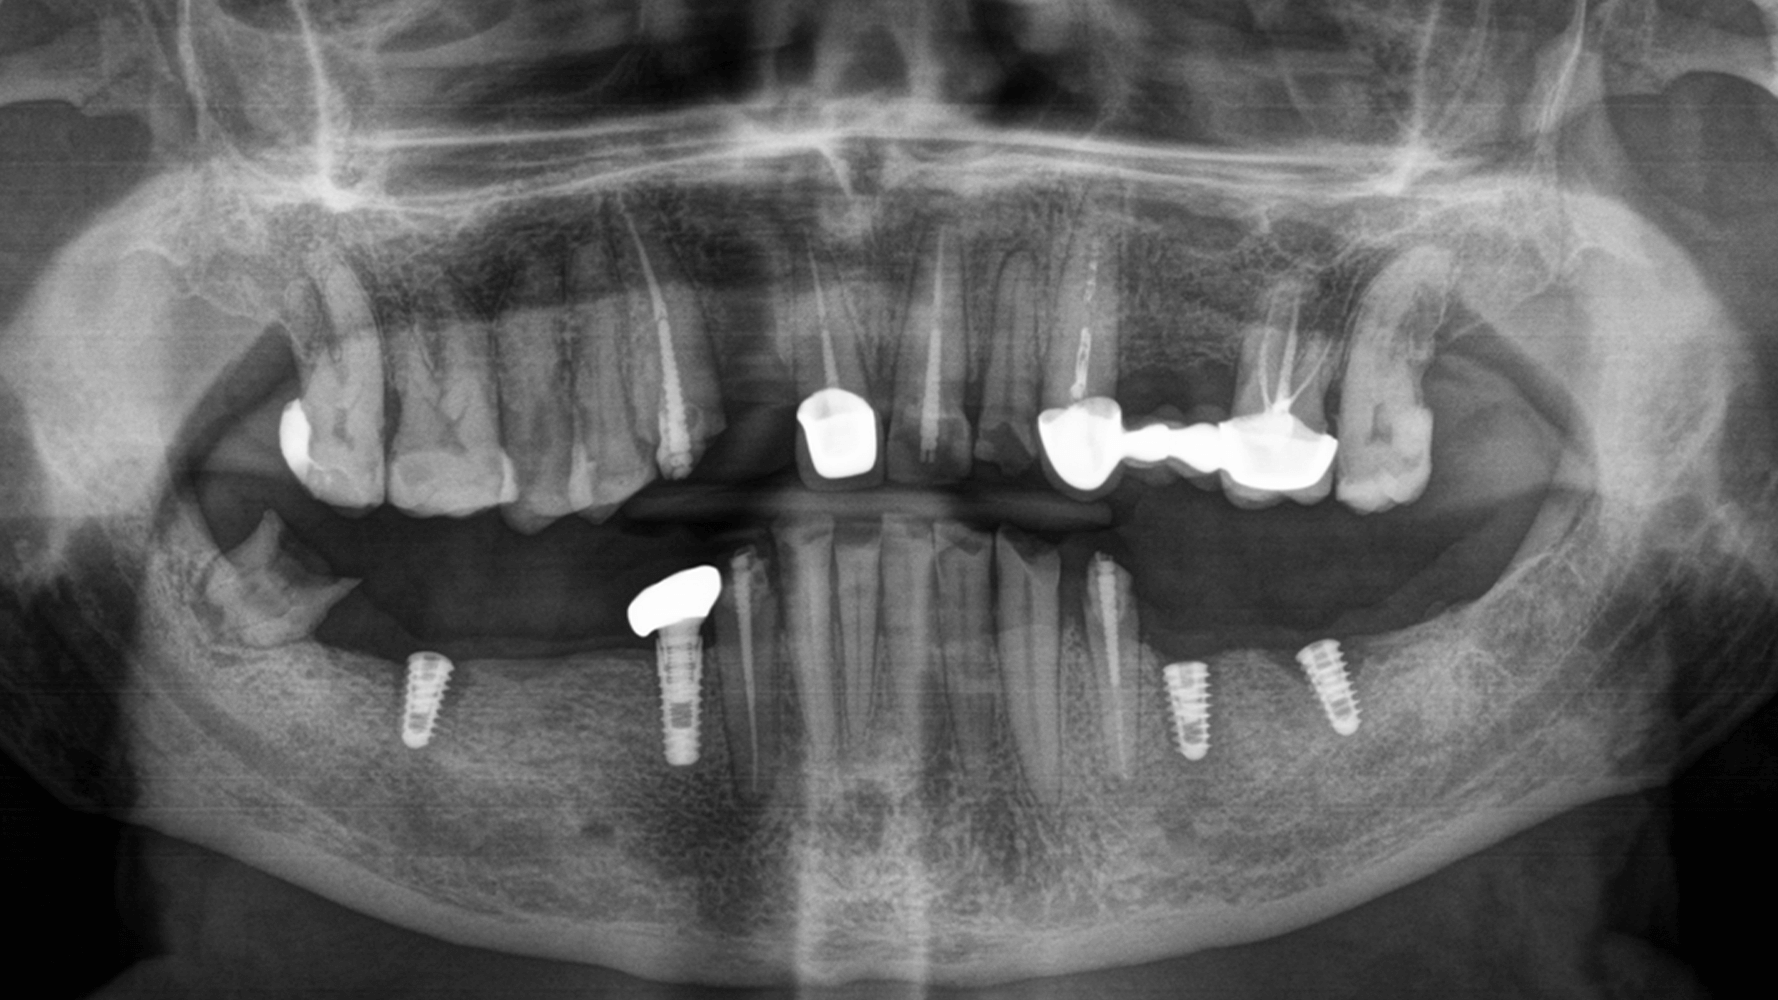

Имплантация зубных имплантов Alpha Dent

За один визит хирург-имплантолог установил 4 зубных имплантата немецкого производителя Alpha Dent.

Протезирование

На основе ранее полученной модели были изготовлены единичные коронки и мостовидные протезы из диоксида циркония. За одно посещение сняли временные конструкции и зафиксировали постоянные как на родных зубах, так и на зубных имплантах.